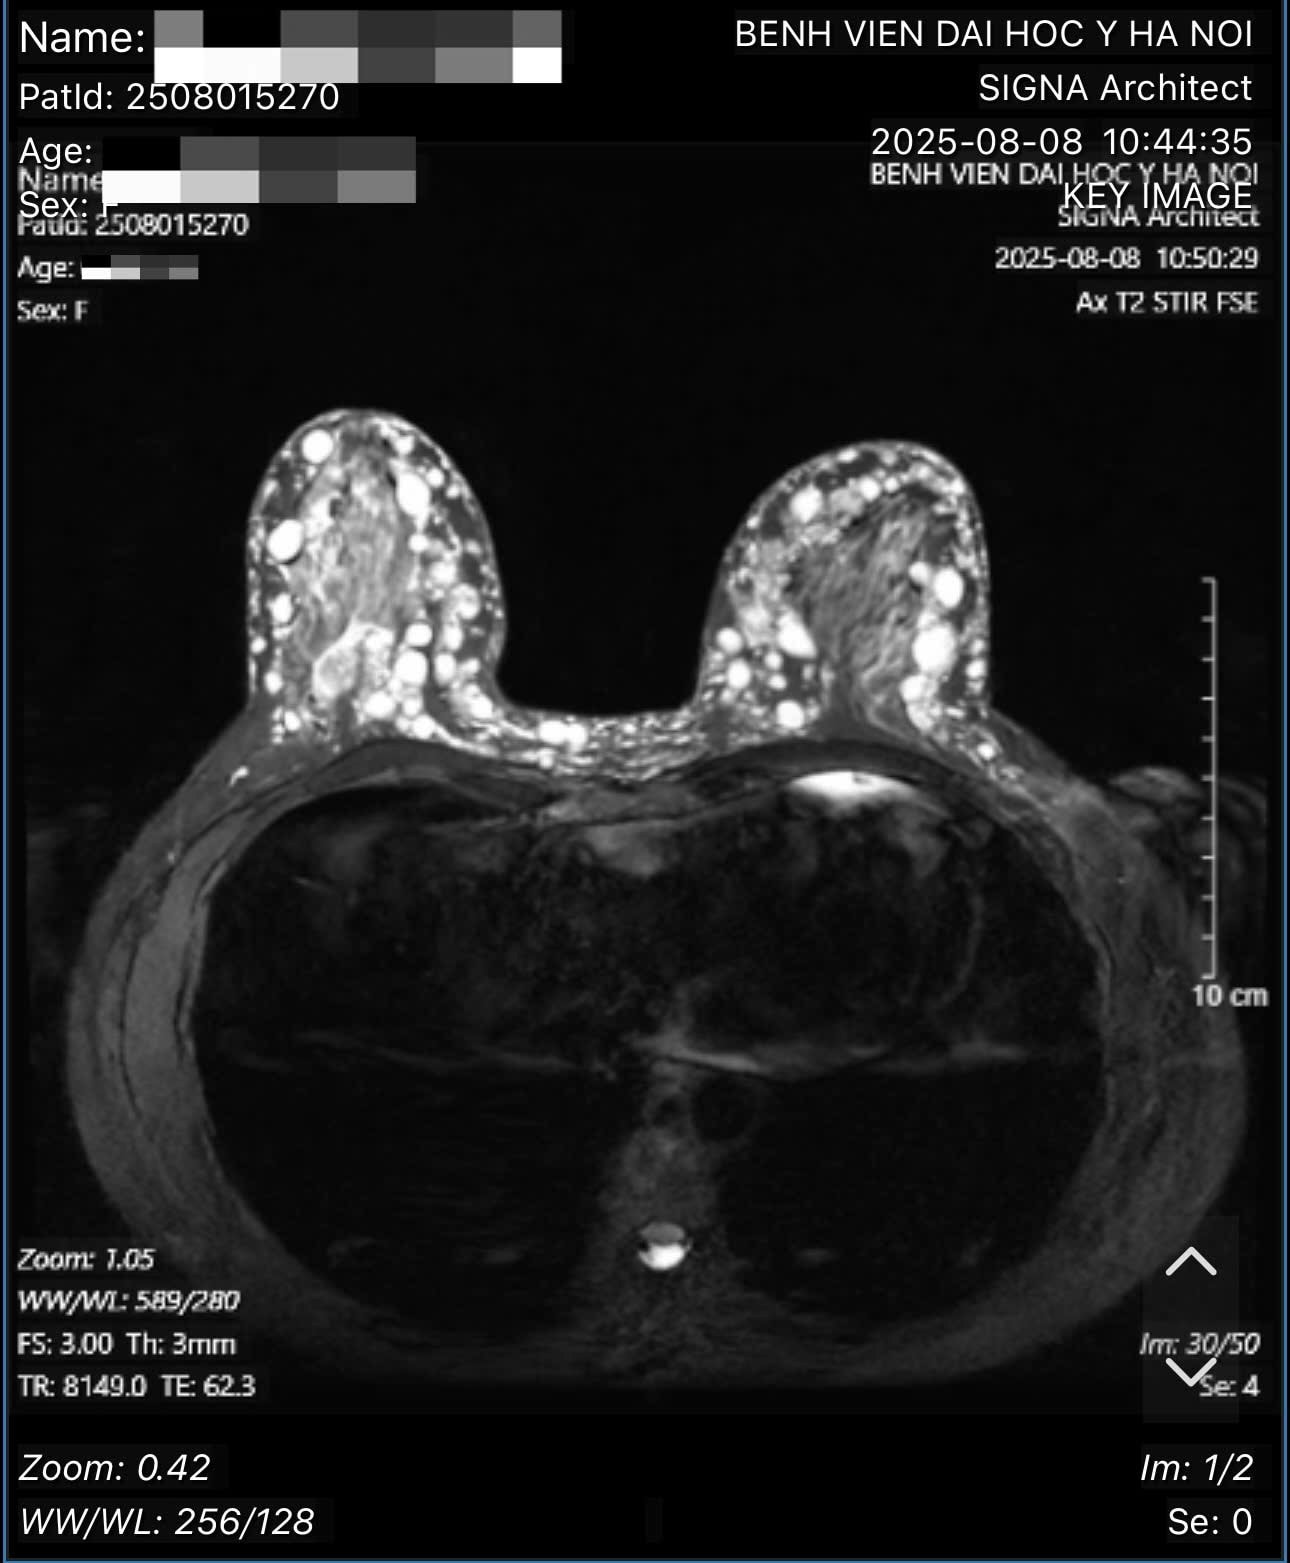

Theo bác sĩ Hồng, qua thăm khám, xét nghiệm và các hình ảnh chụp chiếu, bác sĩ xác định bệnh nhân bị u hạt silicon hai bên ngực (hay còn gọi là siliconoma), thâm nhiễm toàn bộ tổ chức tuyến vú hai bên, đến các tổ chức mỡ dưới da, trung bì da, hay sâu đến lớp cân cơ ngực lớn - là biến chứng của việc tiêm silicon lỏng.

Hình ảnh các hạt sillicone tại ngực bệnh nhân